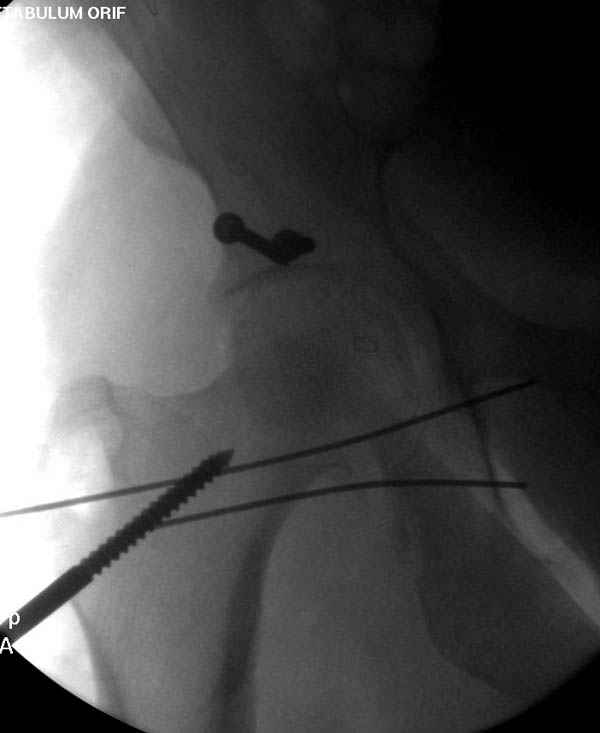

Прооперирован вчера на 13 день после поступления.

Больному 41 и из-за гемодинамической нестабильности в течение первых 7 дней был в реанимации под интубационной седацией.

Кроме перелома плеча у больного старый дистракционный перелом T12-L1 оперированный когда-то и кем-то, открытый перелом костей предплечья, который был прооперирован в ночь поступления, после I&D (хирургической обработки). Из-за разрыва селезенки при поступлении травма хирургами произведено удаление.

Дополнительно имеется перелом ацетабулума: задняя

колонна с полупоперечным переломом, и переломы костей лица.

На седьмой день зафиксирован перелом ацетабулума через задний доступ. Перед операцией для профилактики DVT, IVC фильтер, также получает Lovenox.

Из-за большого обьема конечности доступ к бугорку был затруднен, предварительно зафиксированный шуруп не удержал бугорок, поэтому фиксацию провели толстыми нитками. Состоятельность фиксации бугорка обычно проверяем во время операции, под рентген контролем проводится движения конечности, особенно приведение.